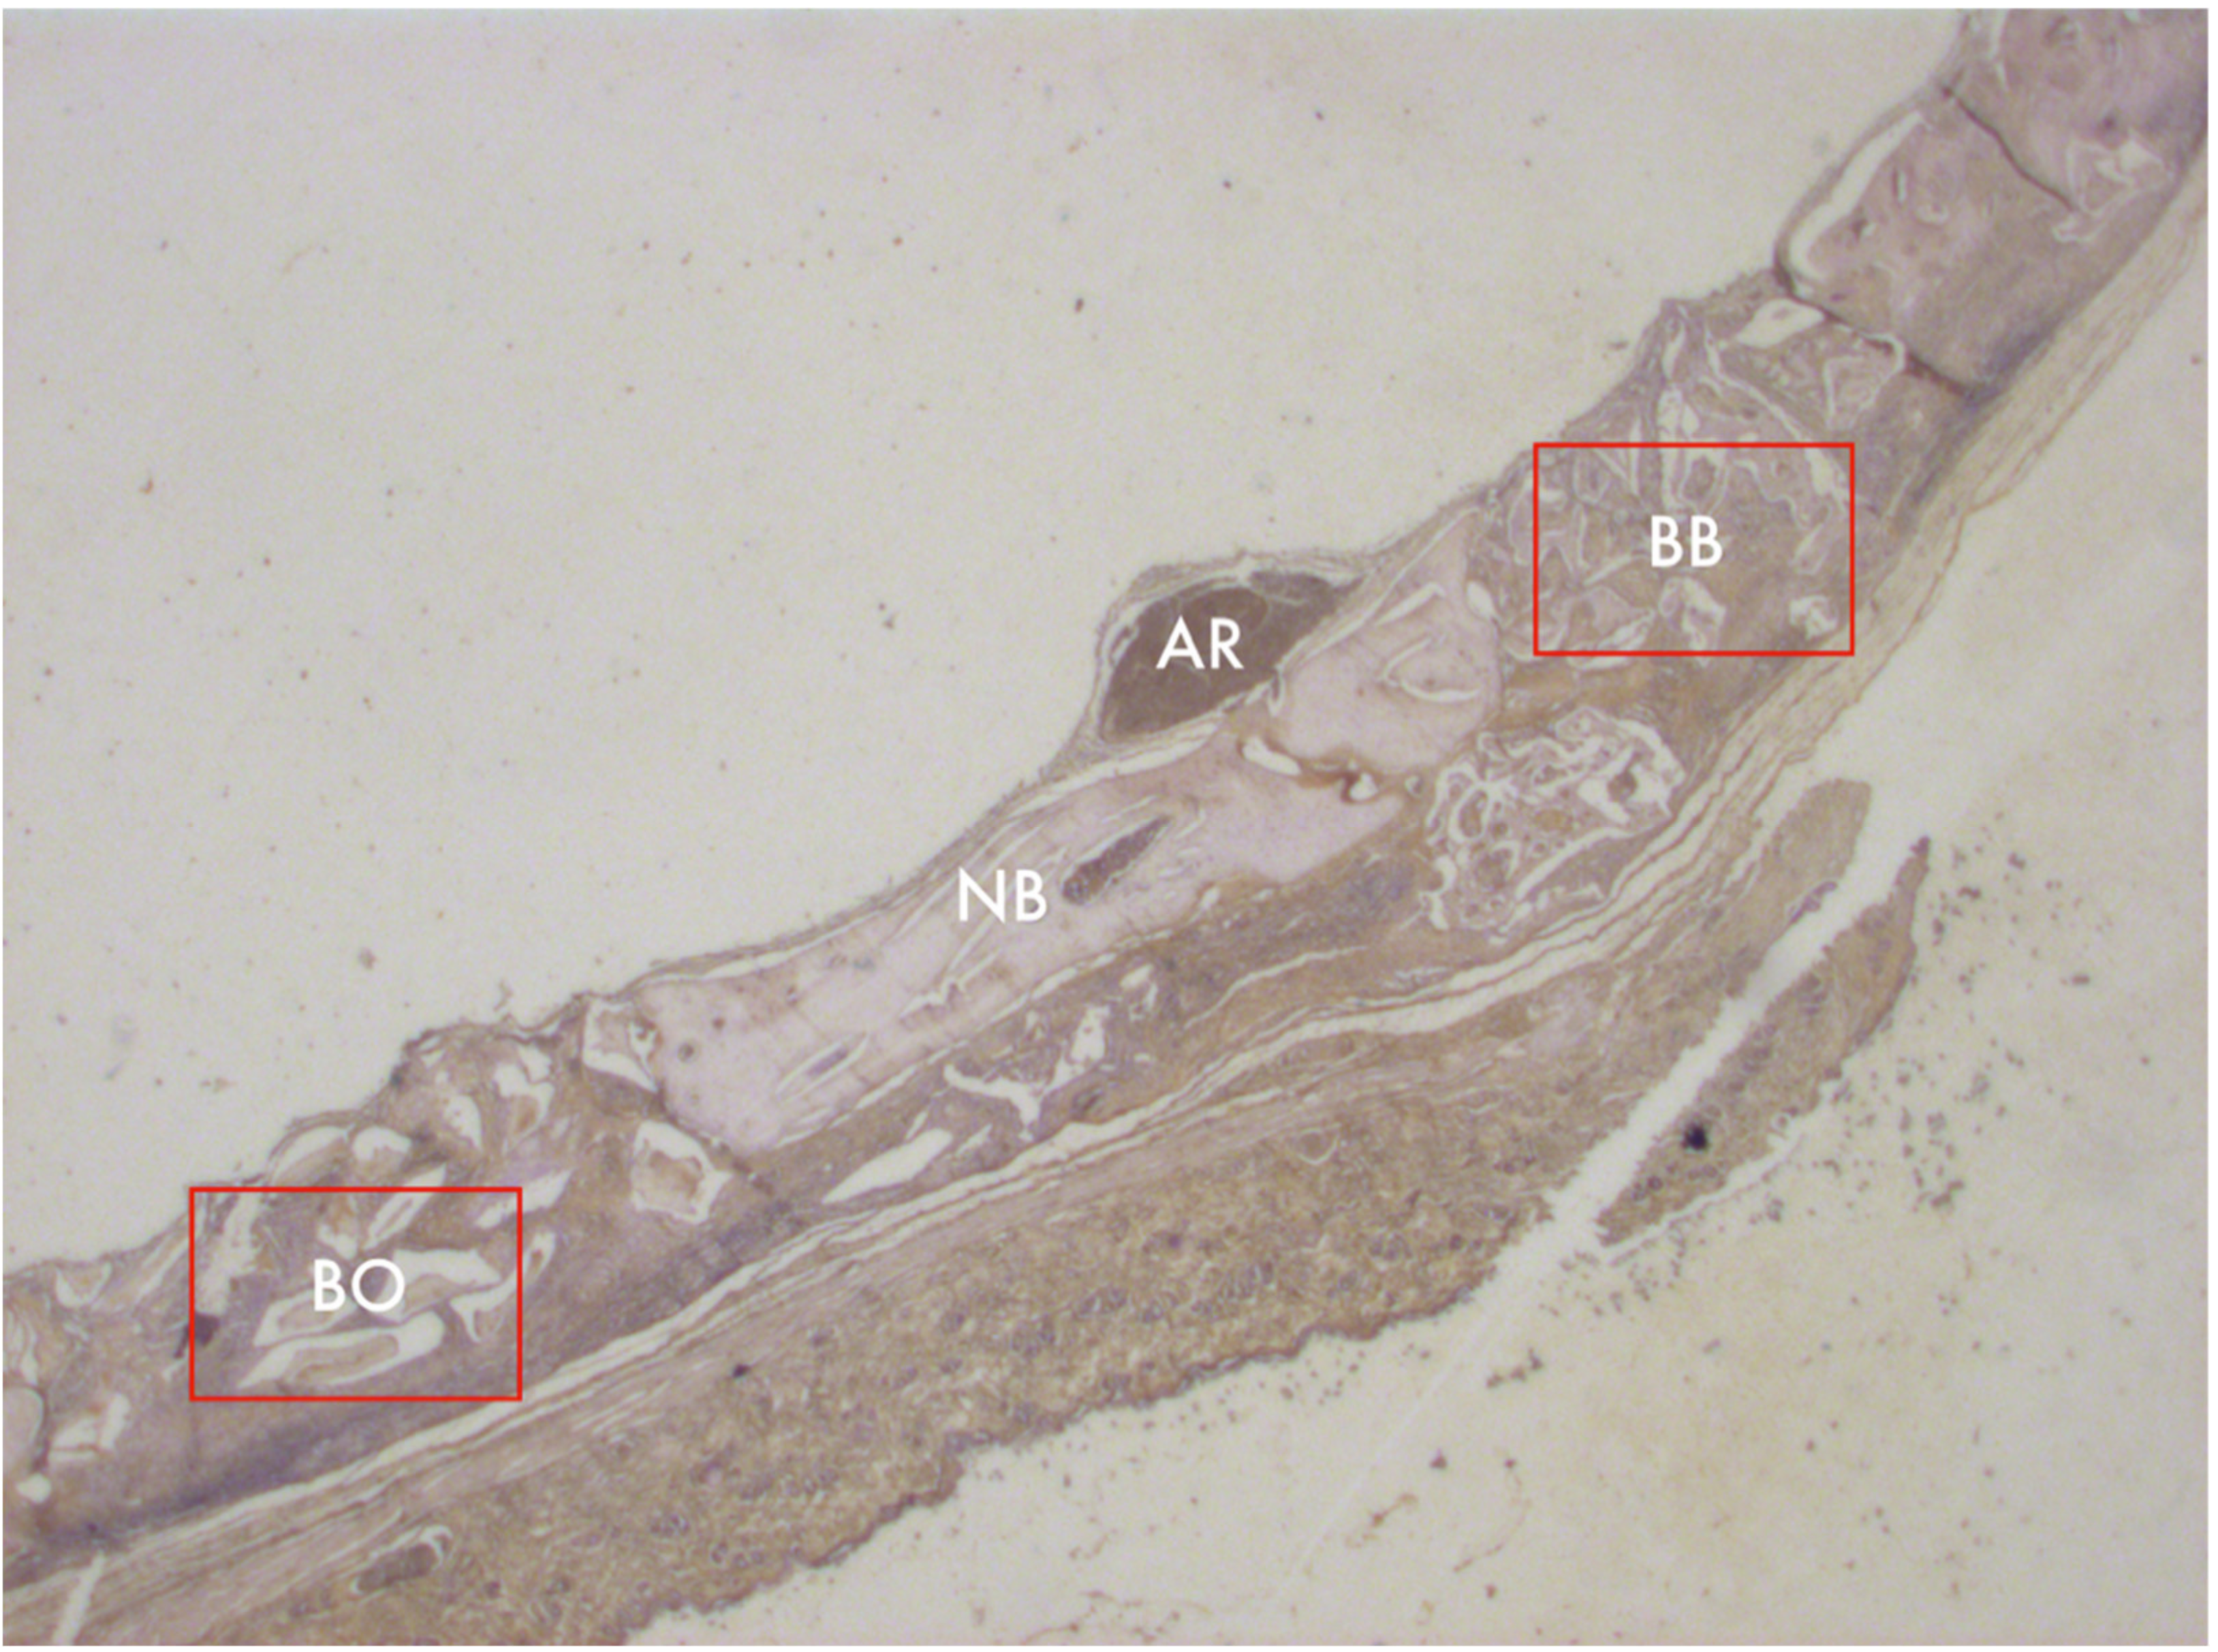

3.2. Masson’s Trichrome Histomorphometry

3.3. PAS Histomorphometry